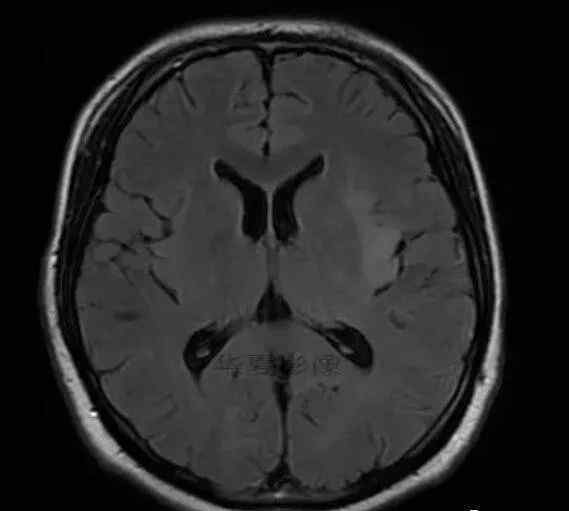

1.左侧颞叶、海马和岛叶T1WI信号低,T2WI信号高

2.病变没有明显的边界

3.占用效果不明显

4.豆状核不受影响